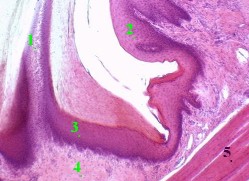

Рисунок с препарата - сагиттальный срез губы ребёнка; окраска

гематоксилин-эозином.

Полный размер